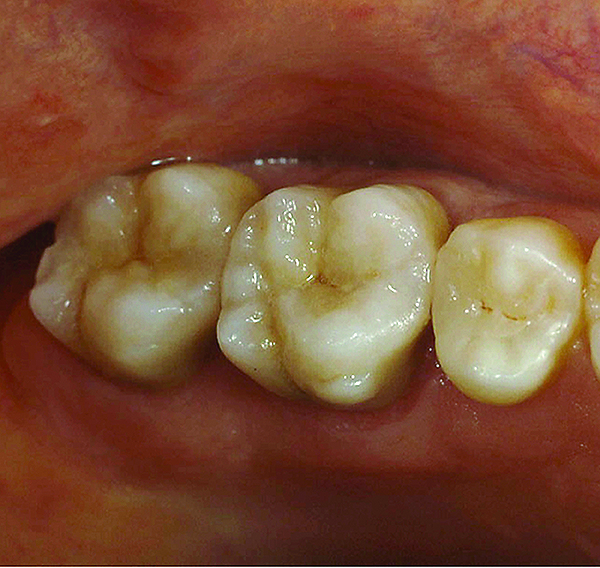

Fig 9. Preoperative view (Fig 9), preparation with composite block-out restoration (Fig 10), and final cementation of CL-IIb material (Fig 11) (final ceramic contour and stain by Steve Lee, CDT, MDC).

Figure 9

Fig 10. Preoperative view (Fig 9), preparation with composite block-out restoration (Fig 10), and final cementation of CL-IIb material (Fig 11) (final ceramic contour and stain by Steve Lee, CDT, MDC).

Figure 10

Fig 11. Preoperative view (Fig 9), preparation with composite block-out restoration (Fig 10), and final cementation of CL-IIb material (Fig 11) (final ceramic contour and stain by Steve Lee, CDT, MDC).

Figure 11